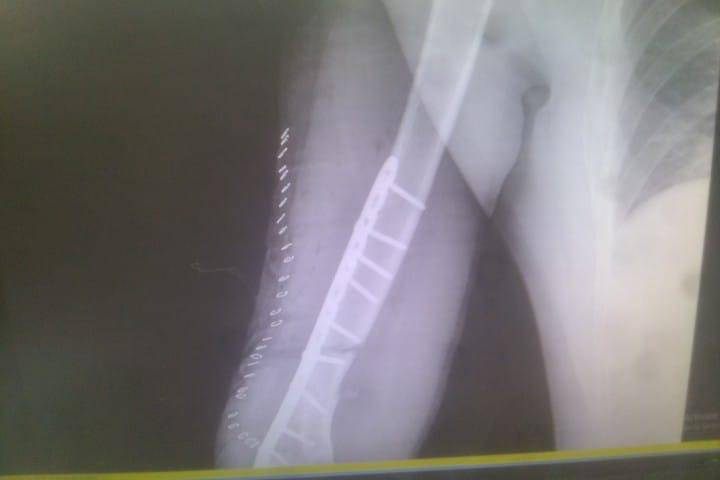

- إجراء عمليات جراحية معقدة و دقيقة في مجال العظام و المفاصل و الكسور و الإصابات ، رغم الضغط الكبير على المستشفى و أعداد المراجعين الكبيرة.

- تطبيق تقنيات جراحية حديثة و متقدمة، و ذلك في ظل التحديات التي يواجهها الفريق بسبب أعداد المرضى و المراجعين الكبيرة.